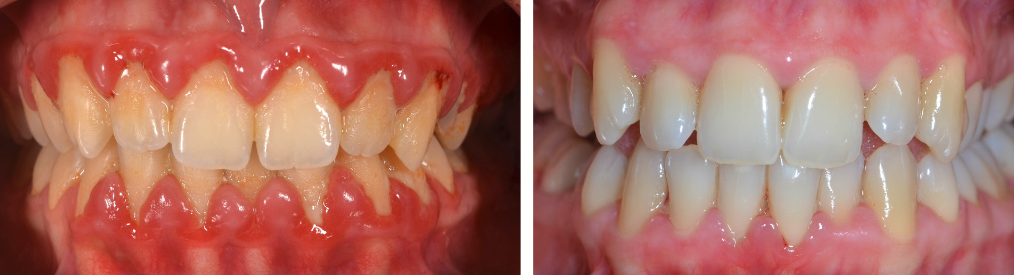

Afecțiunile parodontale sunt una dintre cele mai frecvente probleme ale cavității orale, dar care cel mai adesea rămân nediagnosticate. Acest lucru se datorează adesea simptomelor care nu evoluează proporțional cu gravitatea bolii, ele de obicei rămânând mult mai ușoare, și astfel ajung să fie ignorate o perioadă lungă. Primul și cel mai persistent simptom sunt sângerările gingivale.

În cazul din imagine (Fig. 5.3.4.), s-a realizat inițial tratamentul bolii parodontale, prin detartraje și surfasaje radiculare, asociat cu îmbunătățirea igienei personale. Ulterior, a urmat un tratament protetic fiind realizate coroane metalo-ceramice, ce au restabilit complet funcția masticatorie și estetică. Pacienta revine la cabinet periodic, la fiecare 4 luni, pentru control și igienizare.